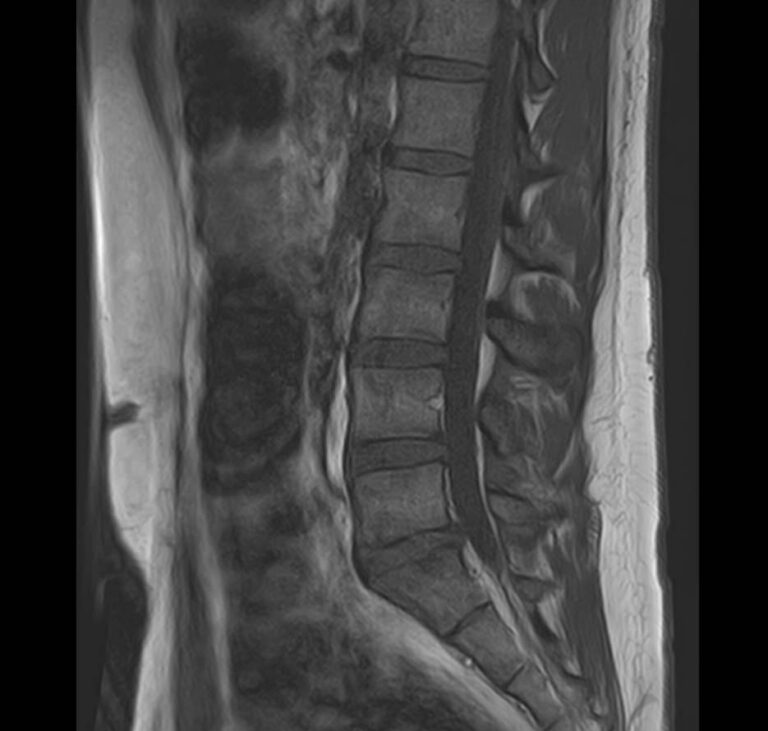

Магнитно-резонансная томография является современным, высокоточным, неинвазивным и безболезненным методом диагностики различной патологии позвоночного столба. Благодаря МРТ можно визуализировать костную структуру позвонков, оценивать состояние спинного мозга на исследуемом уровне, нервных корешков, связочного аппарата и окружающих мягких тканей. В основе метода лежит использование внешнего магнитного поля, которое не оказывает негативного влияния на организм человека. Отсутствие использования ионизирующего излучения делает МРТ безопасным методом исследования и позволяет проводить его достаточно часто по мере необходимости.